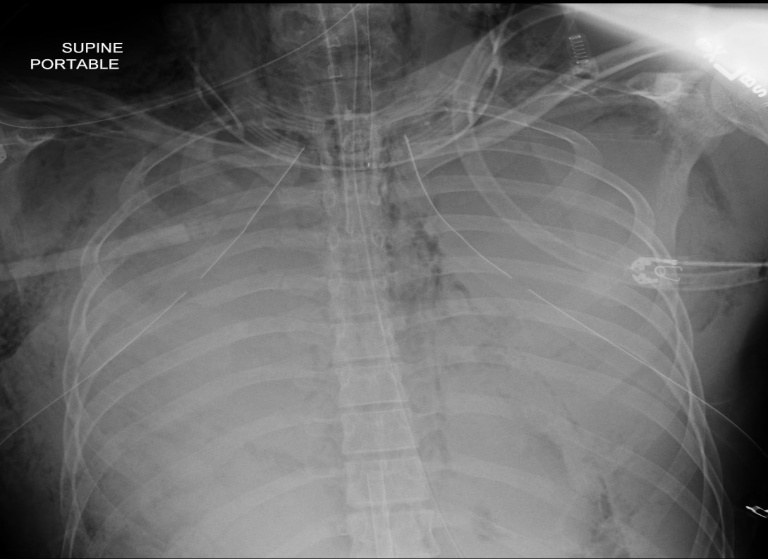

The microscopic examination of the sputum sample after treatment with 40% KOH and special stains revealed no fungal elements. The sputum was cultured in blood, chocolate, MacConkey and Sabouraud dextrose agar. The chest X-ray showed bilateral consolidation in the right lower lobe with veiling air space opacities (fig. 2). The chest CT showed bilateral scattered ground glass opacities and multifocal inhomogeneous consolidation with small cavitary lesions in the middle lobe. It was consistent with pneumonia, extensive subcutaneous emphysema and minimal pneumomediastinum. (fig. 3). Patient was not at risk for contact with Tuberculosis or fungal infection; hence lymph proliferative disorders or Nocardiosis was strongly considered based on imaging morphology. The modified acid-fast staining for sputum and BAL samples showed filamentous weak acid-fast bacilli resembling Nocardia species (fig. 4). The patient did well with Trimethoprim and sulfamethoxazole combination with linezolid and spO2 monitoring, and discharged later. Further follow-up ensured about completion of three months of antibiotics and improvement based on clinical findings and radiologically.

Fig. 2: Chest radiography showed consolidation in the right lower and middle lobe with complete opacification and bilateral hemithorax; apically oriented bilateral chest tubes with end tracheal tube and NG tube in an appropriate position. (Multifocal pneumonia with ARDS)